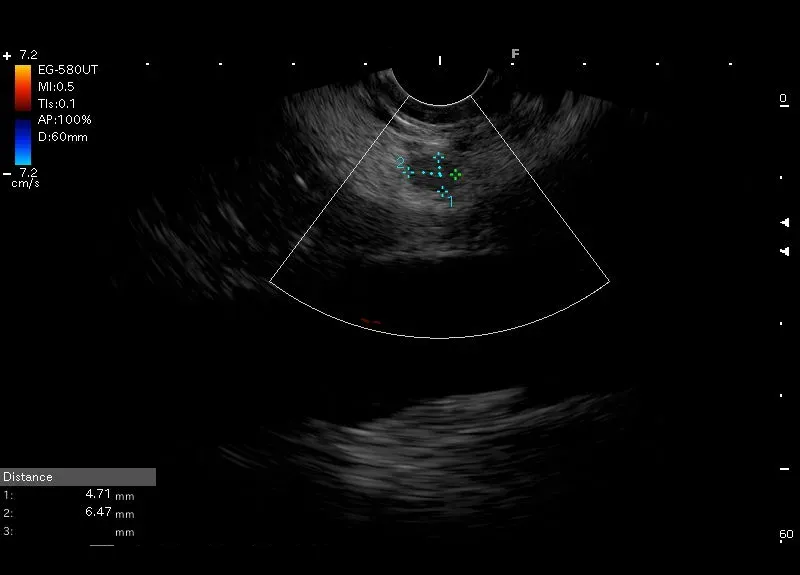

Hipoechogeniczna, regularna zmiana ogniskowa , bez przepływu w opcji Doppler, położona w wyrostku haczykowatym trzustki -obraz sugeruje NET